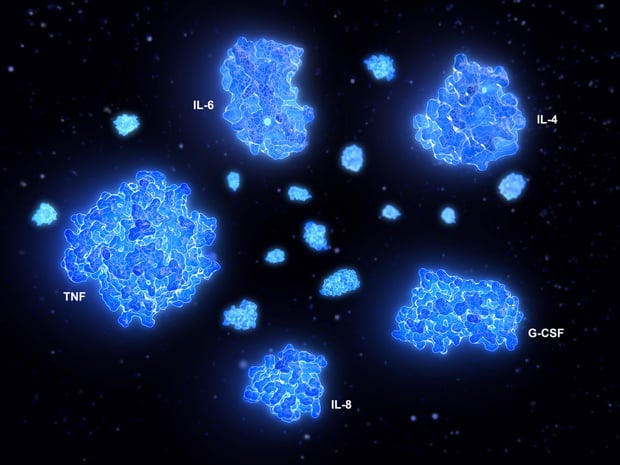

Pour parvenir à cette conclusion, les chercheurs du département de soins intensifs du centre médical universitaire de Radboud ont comparé les taux de trois cytokines essentielles - le facteur de nécrose tumorale (Tumor Necrosis Factor ou TNF), l'interleukine 6 (IL-6) et l'interleukine 8 (IL-8) - dans le sang des patients admis aux soins intensifs avec plusieurs affections distinctes (Covid-19 avec un syndrome de détresse respiratoire aiguë ou SDRA, choc septique bactérien avec ou sans SDRA, arrêt cardiaque ou traumatisme grave). Les concentrations de cytokines ont été mesurées avec les mêmes méthodes pour chaque groupe.

Les concentrations plasmatiques des trois cytokines se sont avérées significativement plus faibles chez les patients atteints de Covid-19 que chez les patients présentant un choc septique avec SDRA. Les concentrations d'IL-6 et d'IL-8 étaient également plus faibles chez les patients porteurs d'un Covid-19 que chez les patients présentant un choc septique sans SDRA. Le taux de TNF était plus élevé chez les patients Covid-19 que chez les patients traumatisés. Il n'y avait pas de différence dans les taux d'IL-6 entre les patients Covid-19 et les patients ayant subi un arrêt cardiaque ou un traumatisme, et les taux d'IL-8 étaient plus faibles chez les patients Covid-19 qu'après un arrêt cardiaque.

Les chercheurs ont trouvé des niveaux similaires de cellules inflammatoires dans le sang de patients atteints de Covid-19 et de patients grippés. Au total, seuls sept patients Covid-19 (un peu plus de 4%) ont montré des signes d'une tempête de cytokines, avec des niveaux extrêmement élevés de cytokines. De plus, la majorité des patients Covid-19 souffrant d'insuffisance respiratoire aiguë non seulement n'ont pas connu cette tempête, mais ils avaient même moins d'inflammation que les patients grippaux qui étaient tout aussi malades qu'eux.